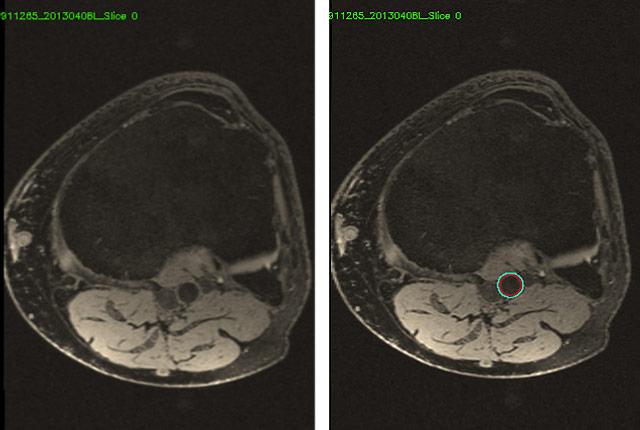

Knee MRIs, of course, are not intended to diagnose atherosclerosis, but rather to reveal sources of musculoskeletal pain. These patient scans had initially been ordered in a study of osteoarthritis. But knee MRIs inevitably include the popliteal artery, which runs vertically behind the knee joint. It has the potential to depict someone’s vascular health as well as vessels nearer the heart.

AI’s magic lies in its speed and consistency. It would be unthinkable for a radiologist to hand-label 3.5 million blood vessels and contours. It only took seven minutes for AI to process one knee scan, versus up to three hours for an experienced human. (One MRI knee series comprises about 70 images, collectively covering about 4 vertical inches of knee joint.)